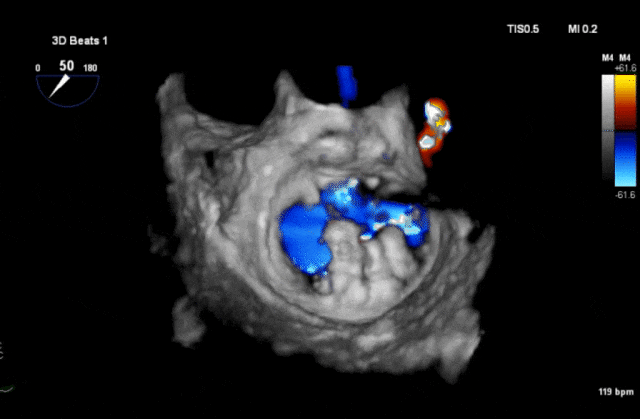

心脏超声示左室增大,二尖瓣2、3区脱垂伴重度反流(腱索断裂),Carpentier分型Ⅱ型,典型Barlow综合征表现;二尖瓣开放面积5.0cm²,3区瓣环内径31mm,前叶长22mm、后叶17mm,前叶收缩期关闭瓣体部分呈拱形突向左房腔,瓣膜游离缘对合欠佳,可见腱索断裂,长度9mm;2区瓣环内径32mm,前叶长22mm、后叶10mm,前后叶均可脱垂;三尖瓣重度反流。CDFI示瓣口重度偏心性反流,反流束沿主动脉后壁走行,肺静脉收缩期可见反向频谱。

术前反流

术前3D